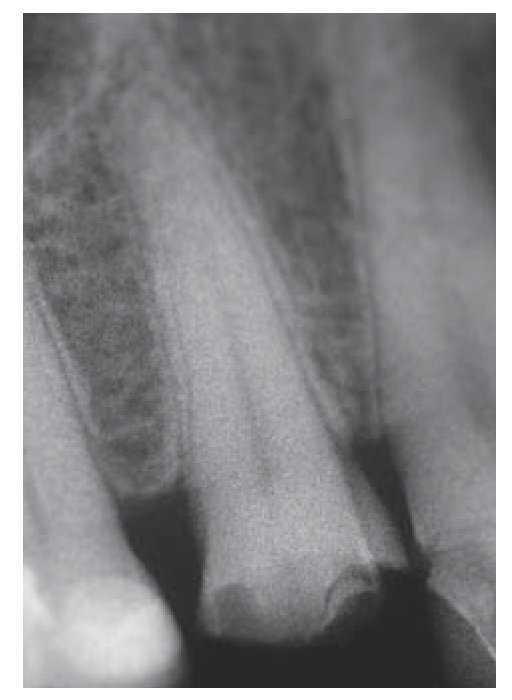

Una paciente de 70 años de edad acude de urgencia a la consulta después de haber sufrido una fractura horizontal nítida del diente 14 (figs. 1 y 2). El diente había sido tratado con un inlay de cerámica MOD en 1993. La paciente indicó que el diente se había fracturado al intentar morder una nuez. El diente conservaba su vitalidad (prueba de vitalidad con aplicación de frío positiva) y no presentaba movilidad (valor de Periotest: +1, es decir, anquilosis leve). Después de inspeccionar el diente con las gafas con lupas de 6 aumentos no se detectaron fisuras radiculares. En la radiografía practicada se observó una cavidad pulpar de tamaño reducido que, sin embargo, no había quedado expuesta como resultado de la fractura (fig. 3).

Figura 3. Radiografía del diente 14.